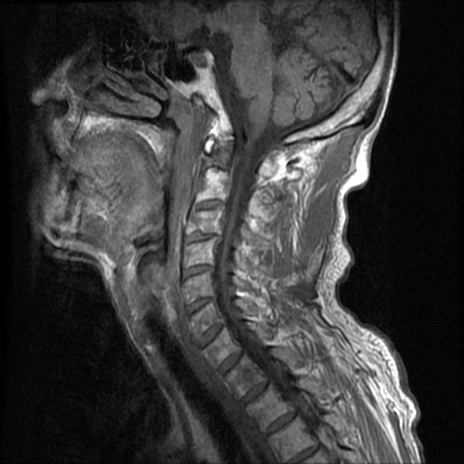

頚椎MRI

T1WI(横断像)

T2*WI(横断像)

T2WI(矢状断像)